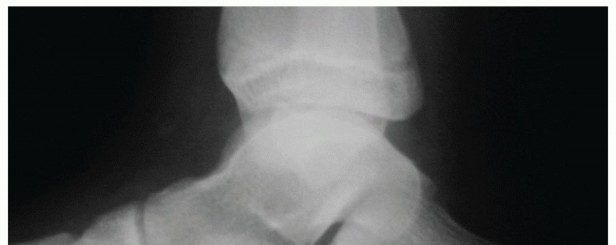

DEFINITION Hallux rigidus is an arthritic condition of the first metatarsophalangeal (MTP) joint. It is the m…